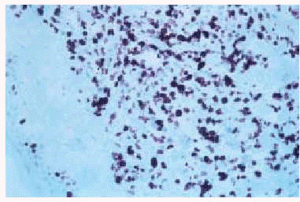

Se solicitó un aspirado de médula ósea en el que se observaba una infiltración de un 22%, constituida por monocitos de aspecto normal (10%) y células de aspecto monocitoide (12%) (fig. 7). En el estudio inmunohistoquímico, de igual forma que en la biopsia cutánea, el infiltrado medular presentó positividad para marcadores de la serie monocito-macrofágica (CD56+, CD14+). Los hallazgos observados en la biopsia de médula ósea eran compatibles con una leucemia mielomonocítica crónica (LMMC). Sin embargo, la ausencia de blastos en sangre periférica no permitía establecer dicho diagnóstico. El caso fue encuadrado en lo que se ha denominado síndromes mieloproliferativos no clasificables. El diagnóstico final fue, por tanto, el de leucemia cutánea aleucémica asociado a síndrome mieloproliferativo no clasificable.

Fig. 7.--Infiltración en la punción aspiración de médula ósea por células de aspecto monocitoide.